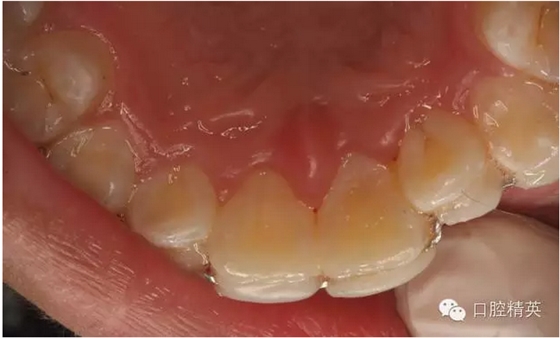

圖1.術(shù)前患者口內(nèi)像、牙槽窩輕度收縮、血凝塊穩(wěn)定、無滲出。